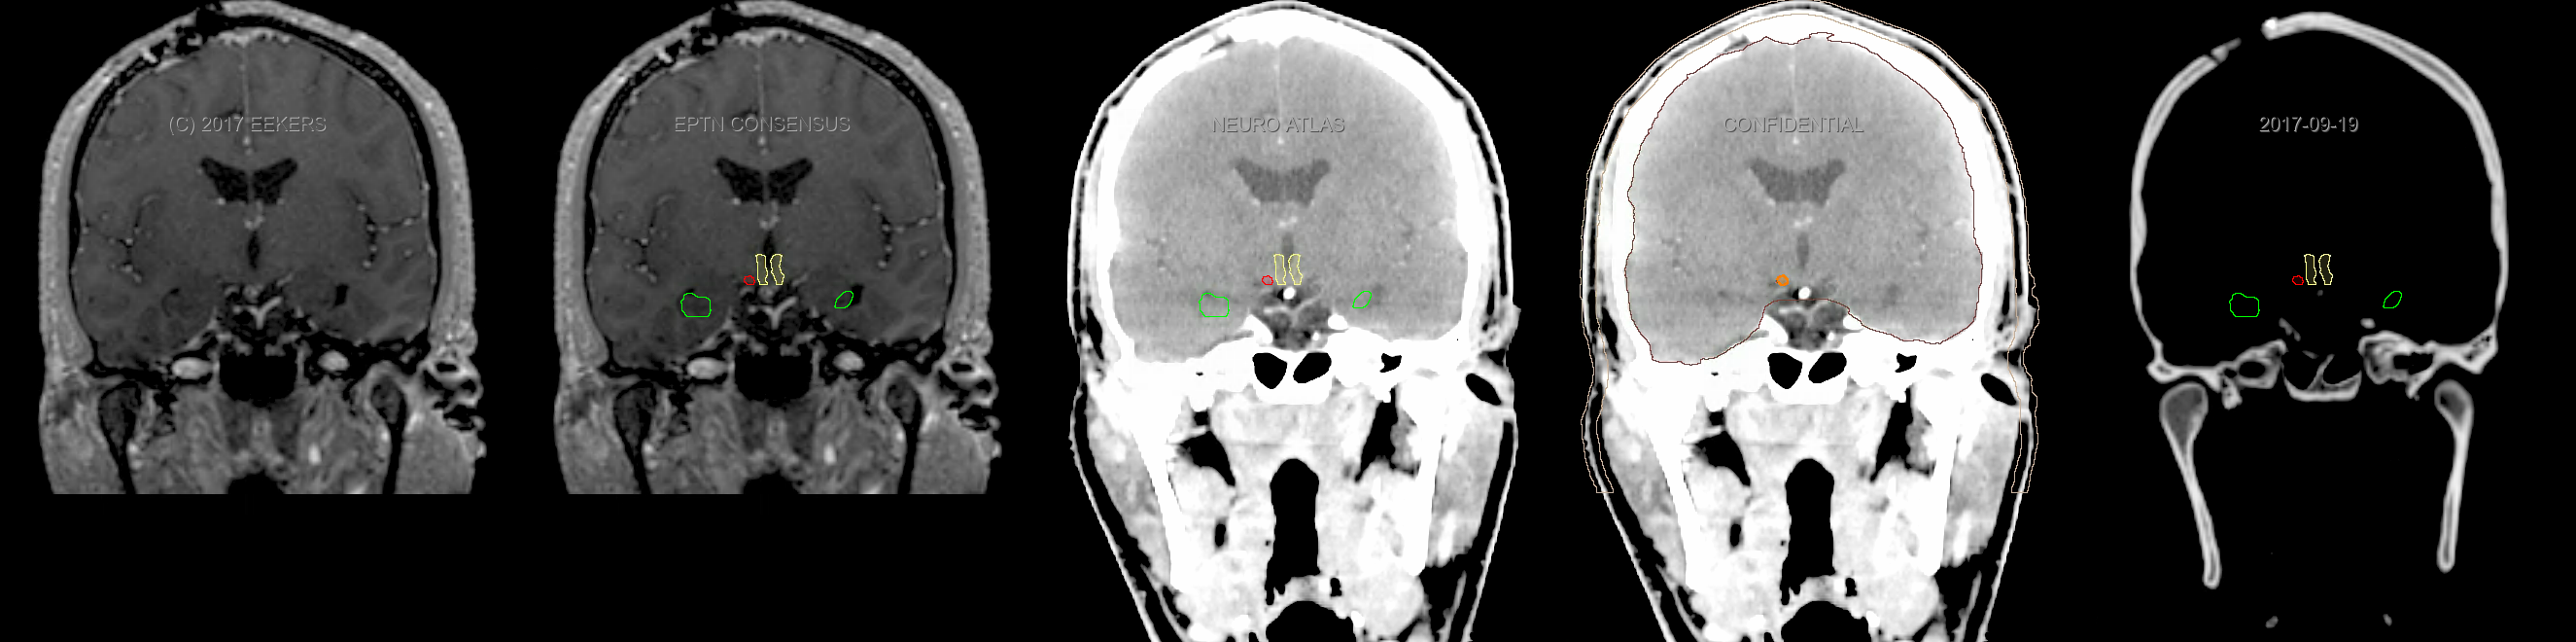

Three-dimensional delineation of the fifteen consensus OARs for neuro-oncology are shown on CT and 3 Tesla (3T) MR images (slice thickness 1 mm with intravenous contrast agent). All are presented in transversal, sagittal and coronal view.

From left to right: MR without structures, MR with structures, CT (WW/WL 120/40) with structures, CT (WW/WL 120/40) with Brain and Brainstem Surface, CT (WW/WL 1500/120)with structures